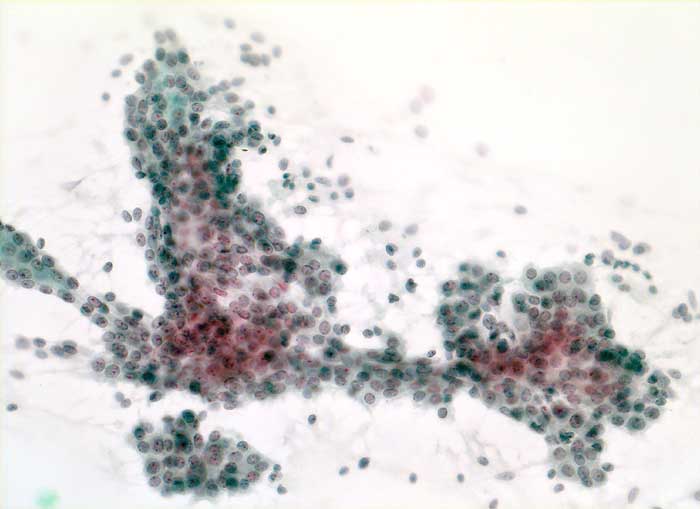

Grosse Mengen epithelialer Zellen, bipolarer Nacktkerne (Myofibroblasten und Fibrozyten) und scharf begrenzte Stromafragmente charakterisieren das Fibroadenom zytologisch. Aspirate von stark fibrosierten Fibroadenomen können auch zellarm sein. Einseitig von Epithel bedeckte Bindegewebsfragmente sprechen für ein Fibroadenom. Durch die Aspiration wird die epitheliale Innenauskleidung mit ihren Verzweigungen aus dem Gangsystem gelöst. Die Epithelverbände sind beim intrakanalikulären Fibroadenom flach und erscheinen beim perikanalikulären Fibroadenom T-, Y-, finger- oder hirschgeweihförmig. Die Kerne sind wenig grösser als die Kerne normaler duktaler Epithelien und messen meist weniger als zwei Erythrozytendurchmesser. Da es sich bei Fibroadenomen um proliferierende Läsionen handelt können die Epithelzellen Zeichen der Aktivierung zeigen in Form einer mässig ausgeprägten Pleomorphie, prominenten Nukleolen, und gelegentlichen Mitosen.

Das erste Beispiel zeigt ein intrakanalikuläres, das zweite Beispiel ein perikanalikuläres Fibroadenom mit stark verzweigten Zellverbänden. Das dritte Beispiel zeigt die Zytomorphologie eines Fibroadenoms mit stark aktivierten Zellen.